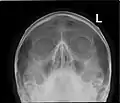

Paranasal sinuses seen in a frontal view